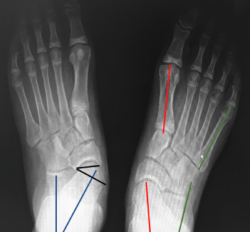

Radiografía dorsoplantar en carga (Figura 5)

Figura 5. Radiografía dorsoplantar en carga. Ángulo Kite (azul). Ángulo C5M (verde). Ángulo del eje del astrágalo y el eje del primer metatarsiano (rojo). Ángulo de descobertura talonavicular (negro).

- Ángulo astrágalo-calcáneo (AC) o de Kite (normal entre 20 y 30°): su aumento es el reflejo de la divergencia AC aumentada en el PPV de componente subtalar.

- Ángulo entre el borde lateral del calcáneo y el eje longitudinal del quinto metatarsiano (C5M): su alteración se correlaciona con la abducción del antepié, siendo su valor normal 0°.

- Ángulo entre el eje del astrágalo y el eje del primer metatarsiano (valores normales de 0 a 5°). Este ángulo es útil para determinar el componente de metatarso aducto. Asociado a una divergencia AC aumentada, orienta a un pie en serpentina o en Z.

- Valoramos la cobertura TN con el ángulo de descobertura TN (valores normales de 10°) o con el porcentaje de descobertura de la cabeza del astrágalo (si > 40%, indica deformidad en abducción severa)(7).